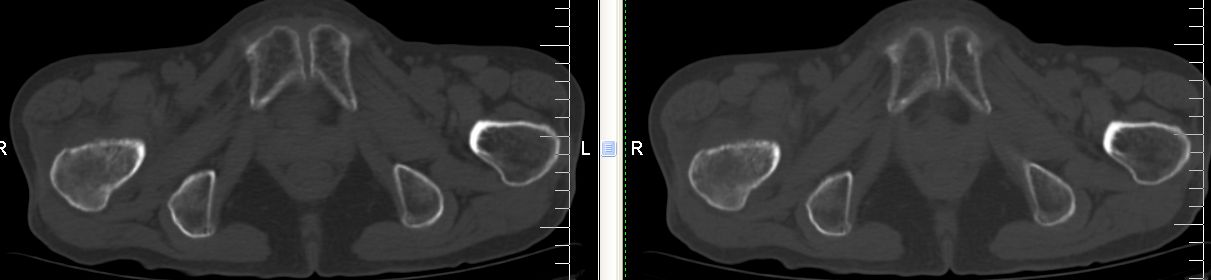

以下是引用余辉在2007-12-5 17:25:00的发言:[br]右侧股骨颈及粗隆区略显膨胀,密度增高略呈不均匀毛玻璃样改变,骨皮质毛糙,考虑1骨纤2骨髓瘤3转移瘤,建议上传软组织窗